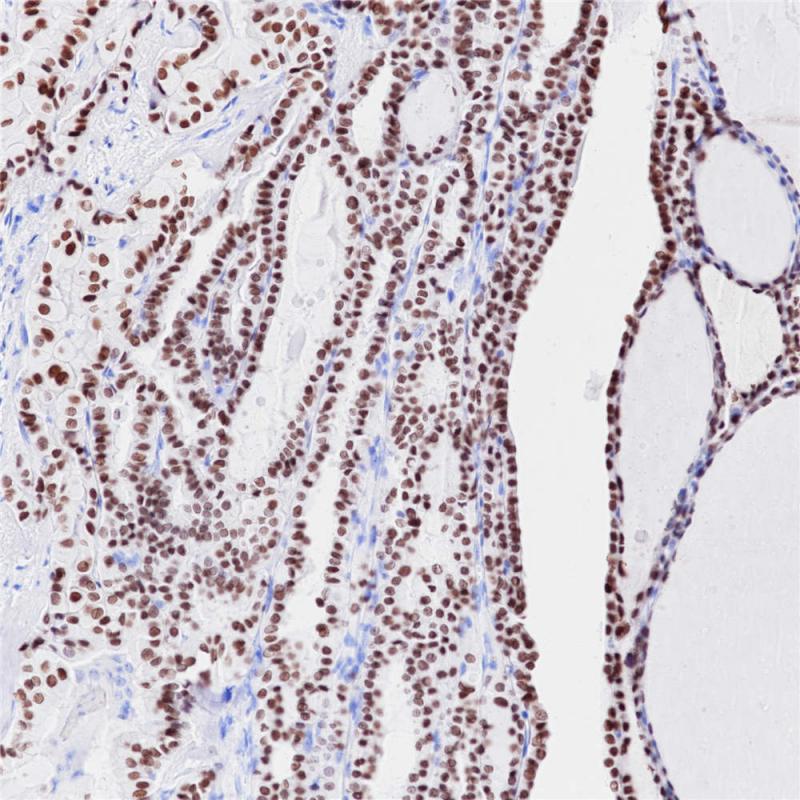

Catenin 是一种分子量为92 kDa细胞骨架蛋白,有α、β、γ三种亚型,与 Wnt 信号传导及细胞粘附机制相关。该抗体可用于鉴别原发性卵巢子宫内膜样癌/卵巢浆液性癌和转移性结肠癌,也可用于间叶性肿瘤、胰腺实性-假乳头状肿瘤的诊断。

阳性对照

前列腺

亚细胞定位

细胞质/细胞核/细胞膜